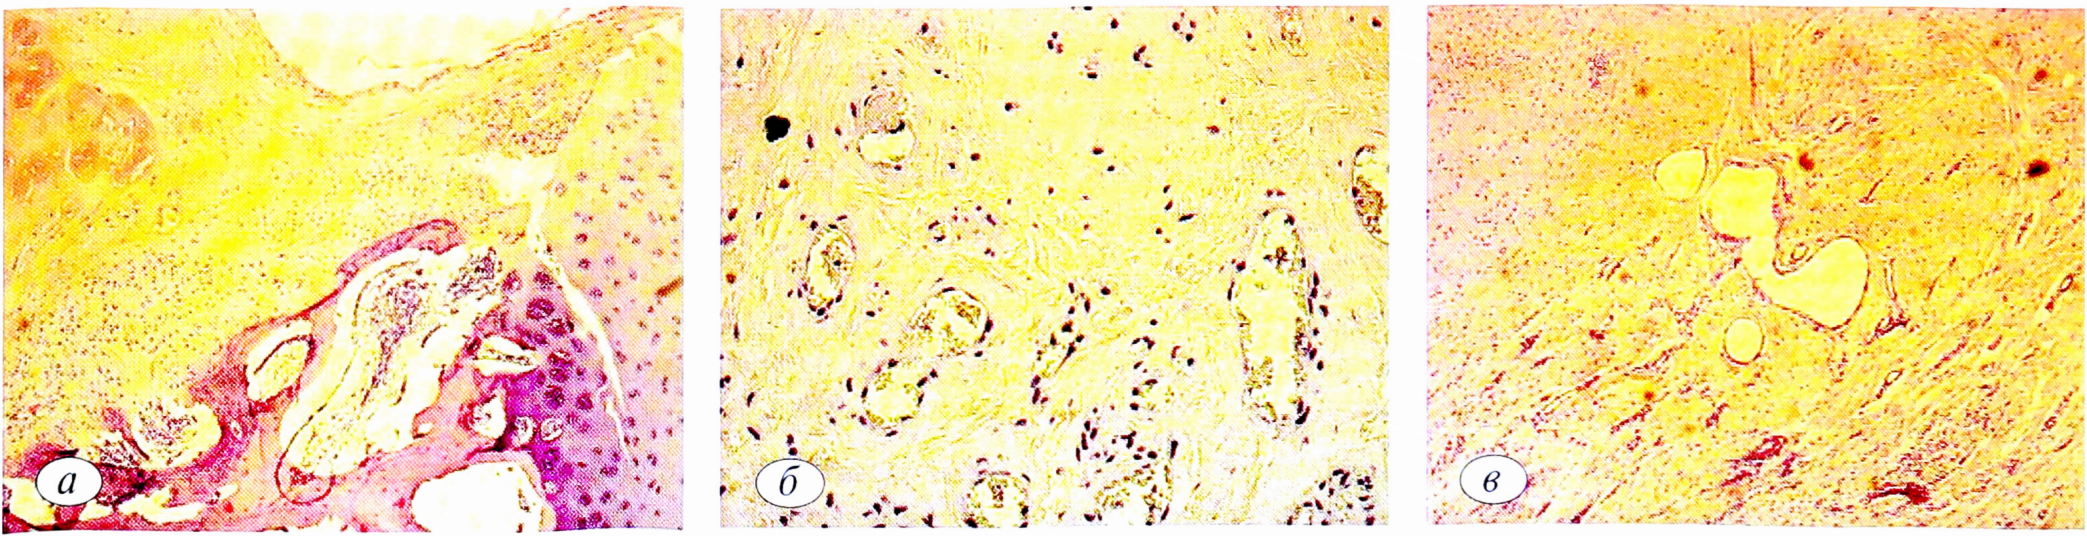

Рис. 4. Динамика микроскопической (после закрытия ВКМ; ув. 40) картины дефекта во 2-й экспериментальной группе. а — через 1 мес; б — через 3 мес; в — через 6 мес.

Fig. 4. Dynamics of microscopic (after the closure of the VCM; UV. 40) pattern defect patterns in the 2nd experimental group. a —after 1 month; б —after 3 months; в — after 6 months.

Во 2-й экспериментальной группе пошагово к 6 мес после операции визуально также определяли минус-ткань. Однако глубина остаточного дефекта была меньше и не превышала 2/3 исходной толщины (рис. 4. а).

Микроскопически в группе с замещением дефекта ВКМ в динамике наблюдали формирование более стабильного, чем в 1-й группе и контроле, регенераторного слоя. К 6 мес эксперимента обнаруживали признаки очагового ремоделирования хрящевой ткани, выражающиеся в формировании хондроцитами колонок-столбиков, некоторое оживление поверхностного слоя (увеличение количества клеток), появление изогенных групп хрящевых клеток в матриксе (рис. 4, б).

Удельный объем клеточных элементов во вновь образованной ткани в этой группе к 6 мес в среднем составил: хондроциты — 5,6±0,3%, хрящевой матрикс — 42±2,1 %, соединительная ткань — 52,3±2,1 %. Средняя глубина дефекта достигала 15,2±2% от толщины нативного хряща.